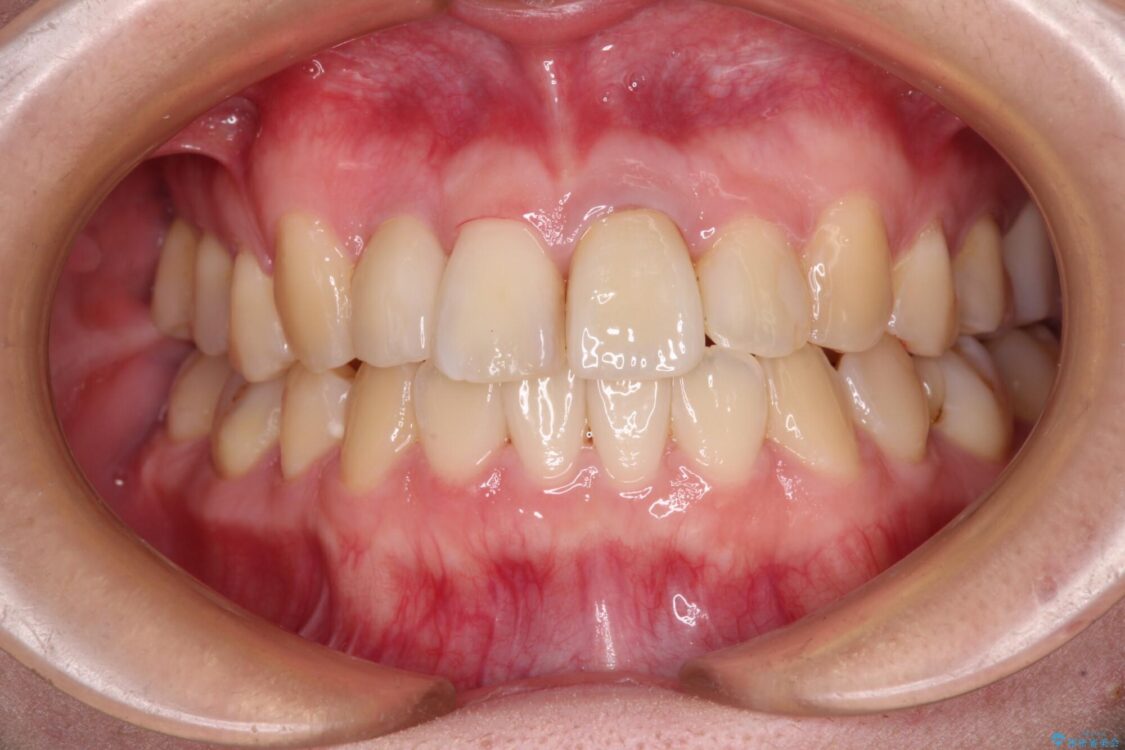

治療前

• 虫歯治療ついでに歯並びの後戻りを改善 インビザラインによる矯正治療 治療前画像